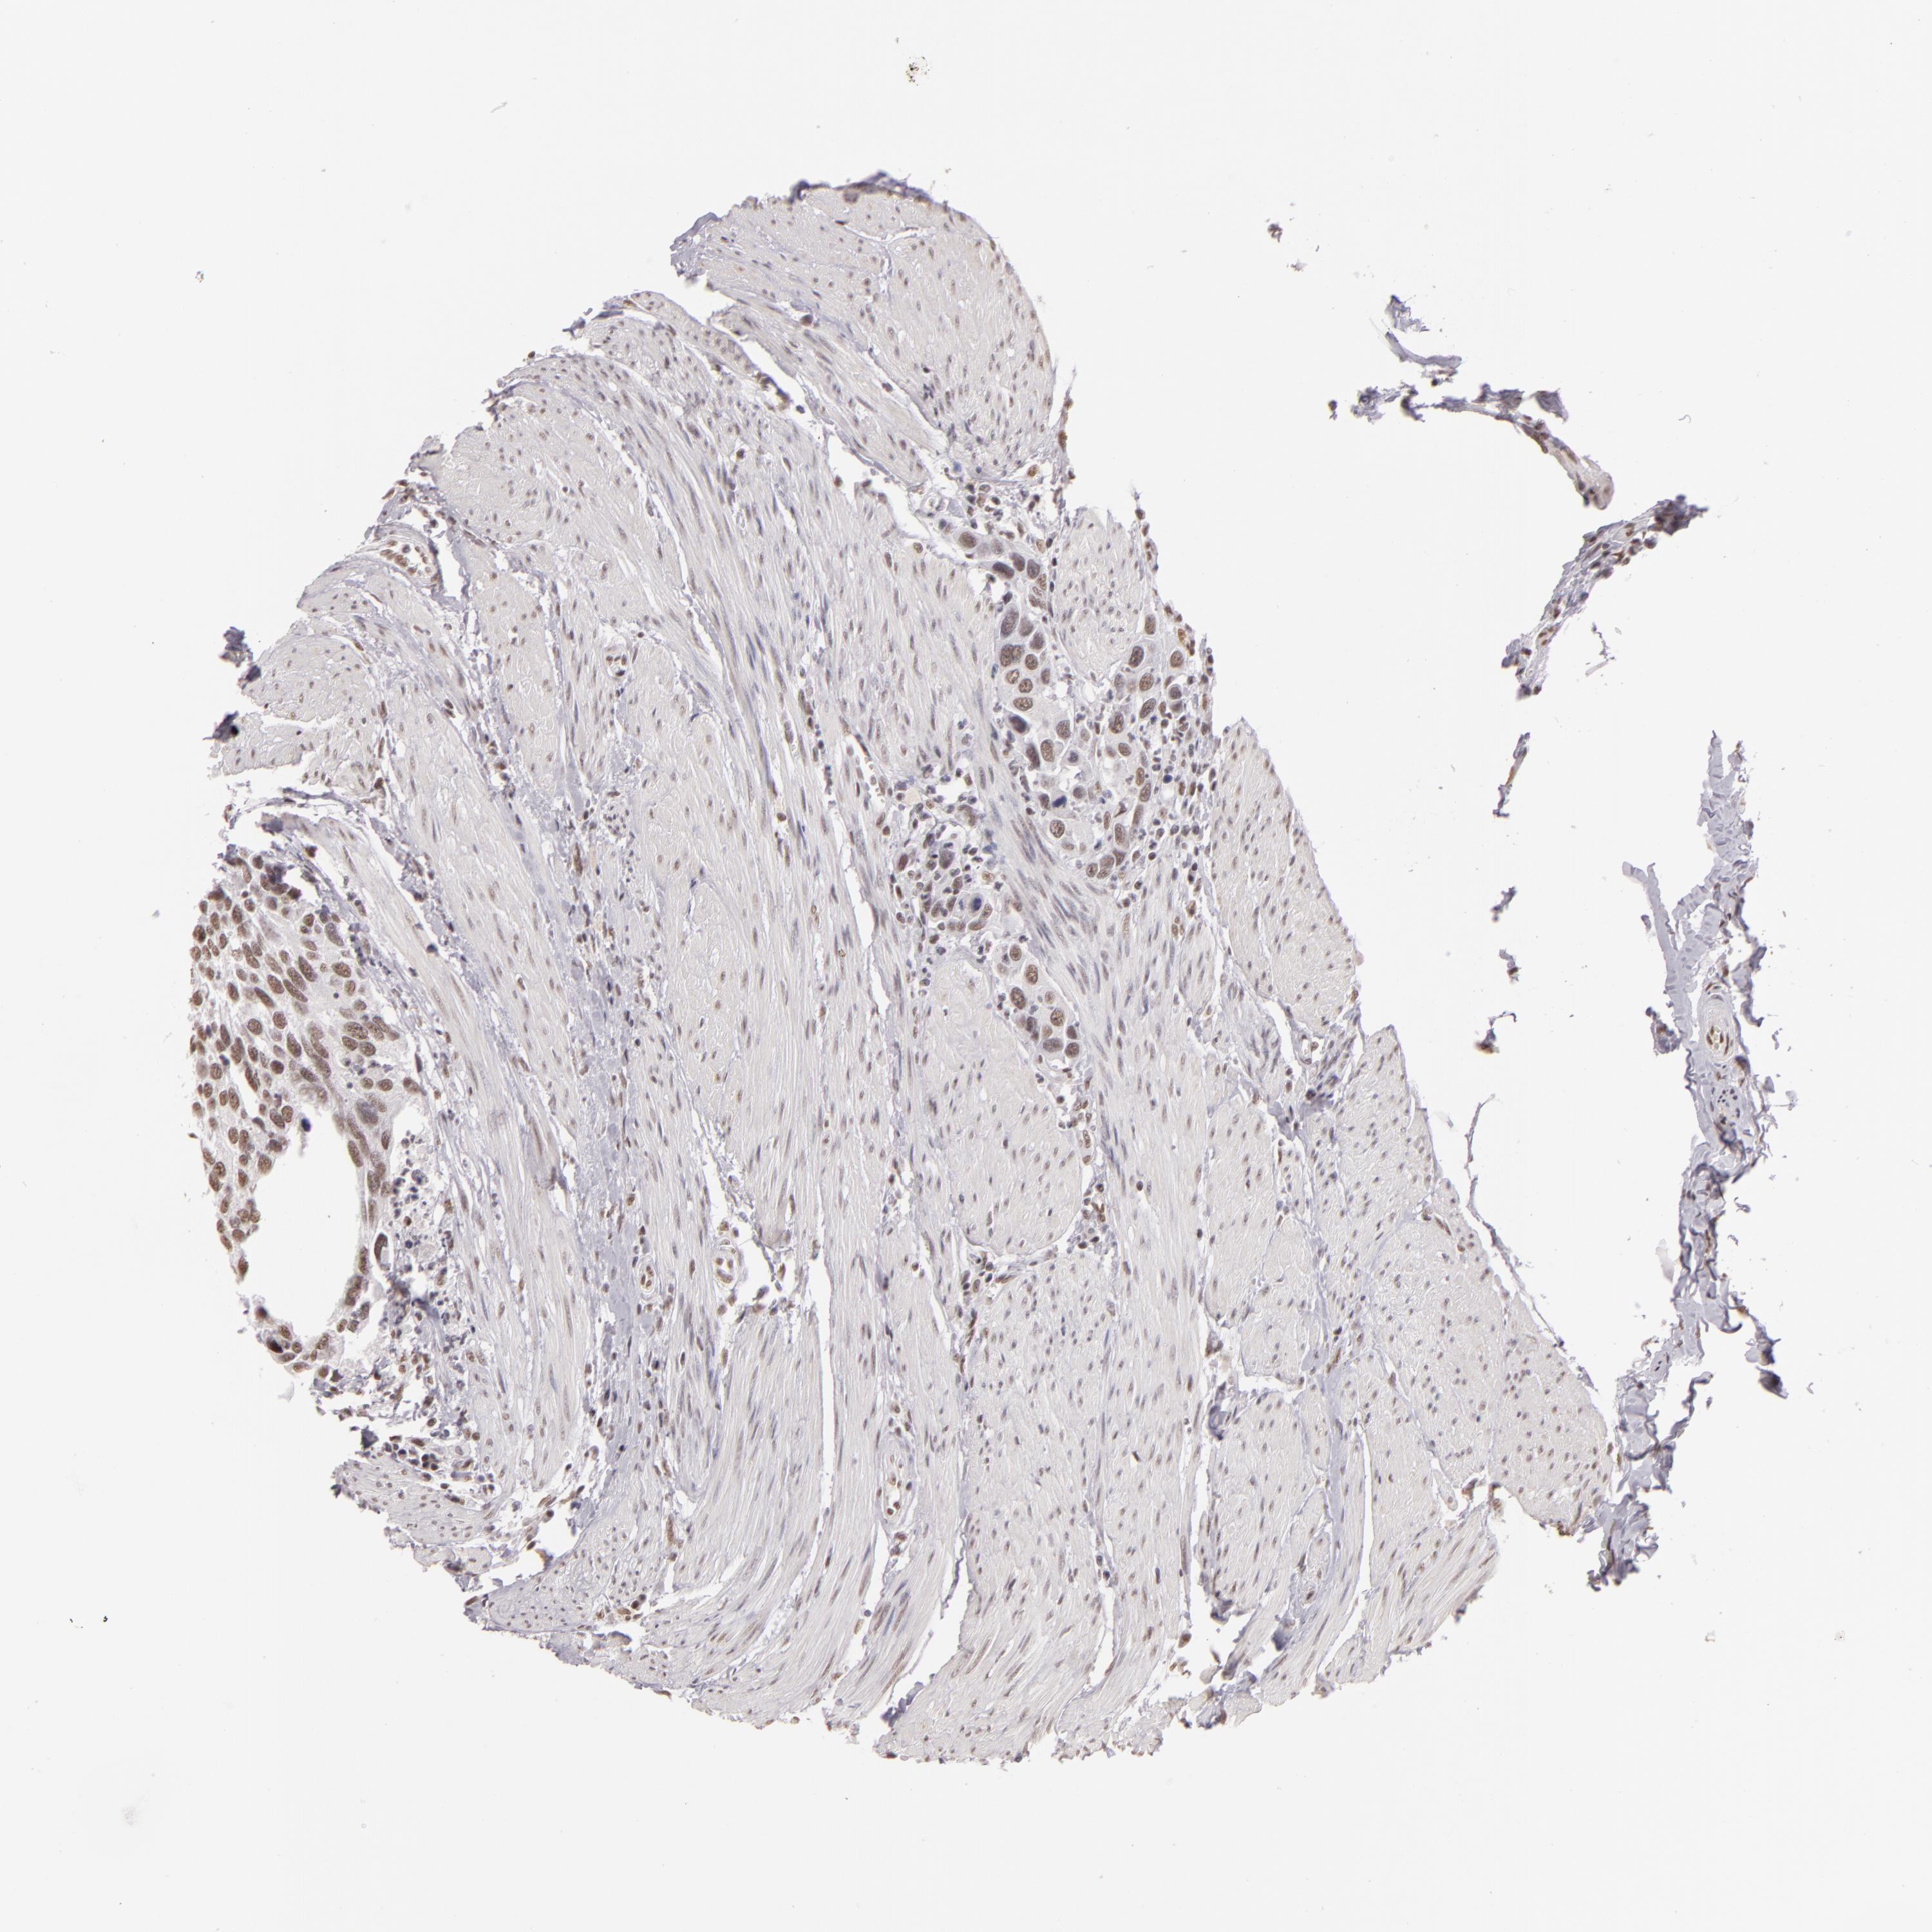

UROTHELIAL CANCER - Protein expressioni

A mouse-over function shows sample information and annotation data. Click on an image to view it in a full screen mode. Samples can be filtered based on level of antibody staining by selecting one or several of the following categories: high, medium, low and not detected. The assay and annotation is described here.

Note that samples used for immunohistochemistry by the Human Protein Atlas do not correspond to samples in the TCGA dataset.

Antibody stainingi

Antibody staining in the annotated cell types in the current human tissue is reported as not detected, low, medium, or high, based on conventional immunohistochemistry profiling in selected tissues. This score is based on the combination of the staining intensity and fraction of stained cells.

Each image is clickable and will lead to virtual microscopy that enables deeper exploration of all samples and also displays staining intensity scores, fraction scores and subcellular localization as well as patient and tissue information for each sample.

Antibody HPA001552

Antibody HPA001846

Staining

High

Medium

Low

Not detected

Intensity

Strong

Moderate

Weak

Negative

Quantity

>75%

75%-25%

<25%

None

Location

Nuclear

Cytoplasmic/membranous

Cytoplasmic/membranous,nuclear

Urothelial carcinoma, High grade

Urothelial carcinoma, Low grade

Adenocarcinoma, NOS